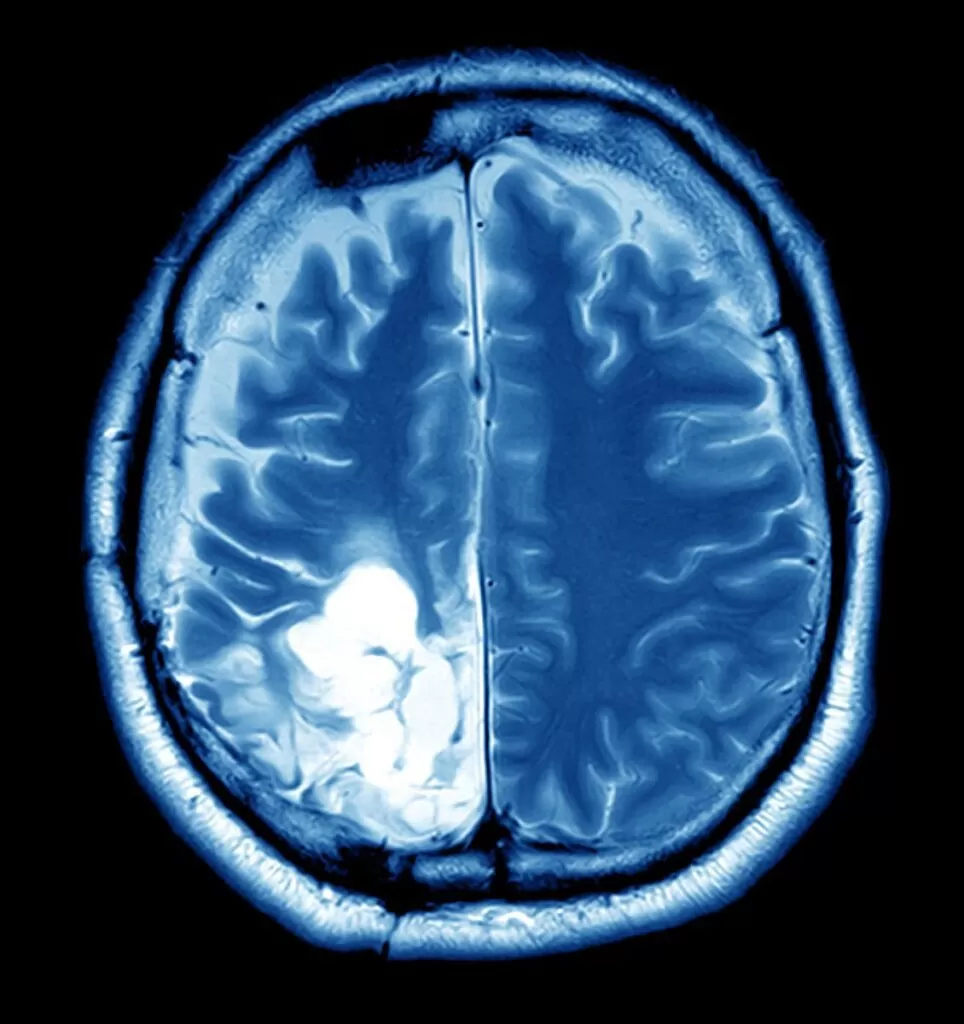

تشخيص ورم عظم الجمجمة يتطلب دقة شديدة ومجموعة من الفحوصات المتكاملة، نظرًا لأن الورم قد يتشابه في أعراضه مع أمراض عصبية أو عظمية أخرى. يبدأ الطبيب عادةً بالتقييم السريري بناءً على شكوى المريض، ثم يطلب الفحوصات التصويرية لتحديد مكان الورم بدقة ونوعه ومدى تأثيره على الأنسجة المحيطة. ويعتبر التشخيص المبكر هو الخطوة الأهم في خطة العلاج الناجح والتقليل من المضاعفات المحتملة.

تشمل أهم وسائل تشخيص ورم عظم الجمجمة ما يلي:

- الأشعة السينية (X-ray): لتحديد وجود أي تآكل أو نمو غير طبيعي في عظام الجمجمة.

- الأشعة المقطعية (CT Scan): تعطي صورًا مقطعية دقيقة توضح حجم الورم وموقعه بدقة.

- الرنين المغناطيسي (MRI): لتحديد تأثير الورم على الدماغ أو الأعصاب القريبة منه.

- الخزعة الجراحية: تؤخذ عينة من الورم لفحصها معمليًا والتأكد من طبيعتها (حميدة أو خبيثة).